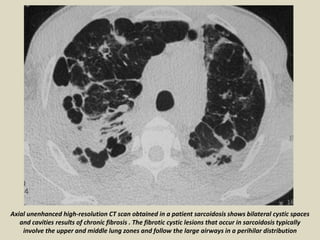

Axial unenhanced high-resolution CT scan obtained in a patient sarcoidosis shows bilateral cystic spaces

and cavities results of chronic fibrosis . The fibrotic cystic lesions that occur in sarcoidosis typically

involve the upper and middle lung zones and follow the large airways in a perihilar distribution